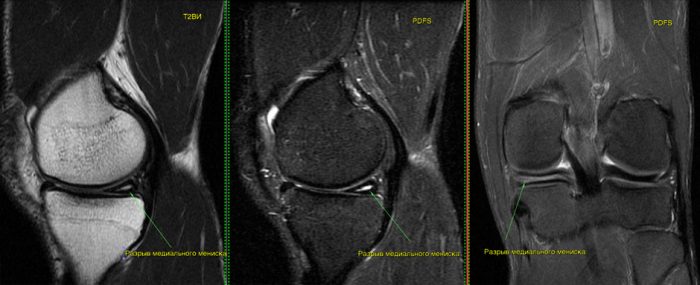

Stoller 2 степени как лечить

Stoller 2 степени как лечить 116 фото